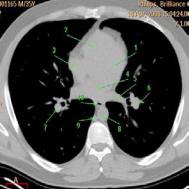

Рис. 29. КТ на уровне ствола ЛА в

средостенном электронном окне:

1– восходящая аорта; 2 – ствол легочной артерии;

3– верхняя полая вена;

4– ветвь правой легочной артерии;

5– левый главный бронх;

6– правый главный бронх;

7– нисходящая аорта;

8– пищевод